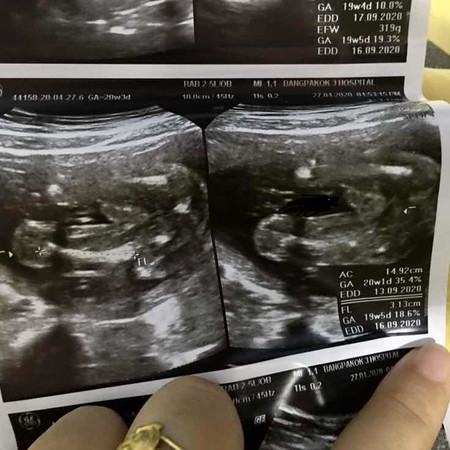

คุณแม่คนไหนที่เคยซาว ว่าได้ผู้ชาย แบบนี้คือชายใช่ไมค่ะ บอกทีค่ะลูกคนแรกค่ะแม่ๆๆ ขอเสียงหน่อยค่ะ??